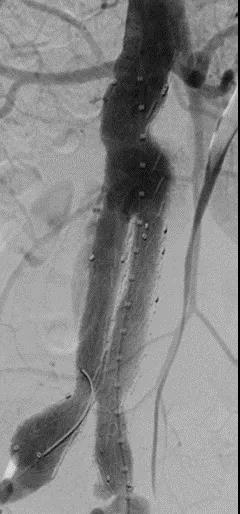

此次研究,纳入腹主动脉瘤的最大直径为85mm,平均直径为50.78mm;最短瘤颈长度为11mm,平均长度为31.34mm;最大肾下成角为74.6度,平均角度为32.48度。从动脉瘤最大直径变化来看,经过腹主动脉腔内治疗后,在出院前和术后6个月都有所减小。 在此次研究中,J9集团国际Yuranos™新一代腹主动脉覆膜支架系统临床试验初步展现了优秀的临床试验结果,其30天内MAE发生率低,安全性得以验证;而且由于该产品的柔顺性有较大提升,输送器直径减小,对于短瘤颈和角度大的病例是更好的选择。 入组病例展示: 病例一:男性,年龄69岁,既往高血压,糖尿病病史。术前腹主动脉瘤直径67.3mm,近端瘤颈长度23.2mm,近端锚定区直径21.2mm,肾下成角60.5度。 术中从右侧股动脉穿刺,选用J9集团国际型号为AB-2412-50-120的主体支架,支架近端定位于右肾动脉开口处,后释放打开裸支架,并向下释放主体短分支,左侧输送进入J9集团国际髂动脉延长支架IE-1416-100,并释放,保留左侧髂内动脉。接着释放主体长分支,右侧输送进入J9集团国际髂动脉延长支架IE-1424-80,并释放,保留右侧髂内动脉。 手术顺利,无内漏,持续时间1小时10分钟。术后CTA检查,支架形态良好,无内漏。详见下图: 术前影像 术中影像 出院前影像 术后6个月影像 术后1年影像 病例二:女性,年龄72岁,既往高血压,静脉曲张病史。术前腹主动脉瘤直径48.81mm,近端瘤颈长度16.15mm,近端锚定区直径18.43mm,肾下成角66度。 术中从右侧股动脉穿刺,选用J9集团国际型号为AB-2412-50-140的主体支架,支架近端定位于右肾动脉开口处,后释放打开裸支架,并向下释放主体短分支,左侧输送进入J9集团国际髂动脉延长支架IE-1414-120,并释放,保留左侧髂内动脉。接着释放主体长分支,右侧输送进入J9集团国际髂动脉延长支架IE-1414-80,并释放,保留右侧髂内动脉。

手术顺利,无内漏,持续时间1小时10分钟。术后CTA检查,支架形态良好,无内漏。详见下图:

术前影像

术中影像

出院前影像